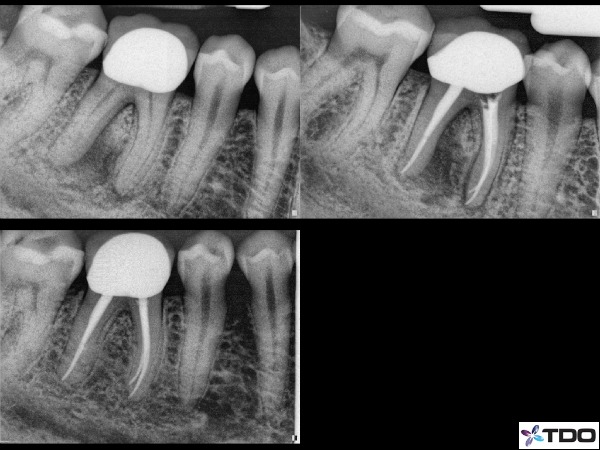

Fig.1 Here is a case of a furcal lesion treated by Dr. Michael Sherman. In the radiograph in the upper right you can see a small lateral canal on the mesial root communicating with the furcation. That lateral canal is filled with sealer and the 2 year recall shows excellent healing.

Fig. 3 This was a retreatment case by Dr. Sherman in which he medicated the canals over 3 appointments using CaOH. The upper left is the pre-operative x-ray. Upper right is the immediate post-operative x-ray and the lower x-ray is the 1 year recall. There has been significant bone fill into the furcation which will continue to improve over time.